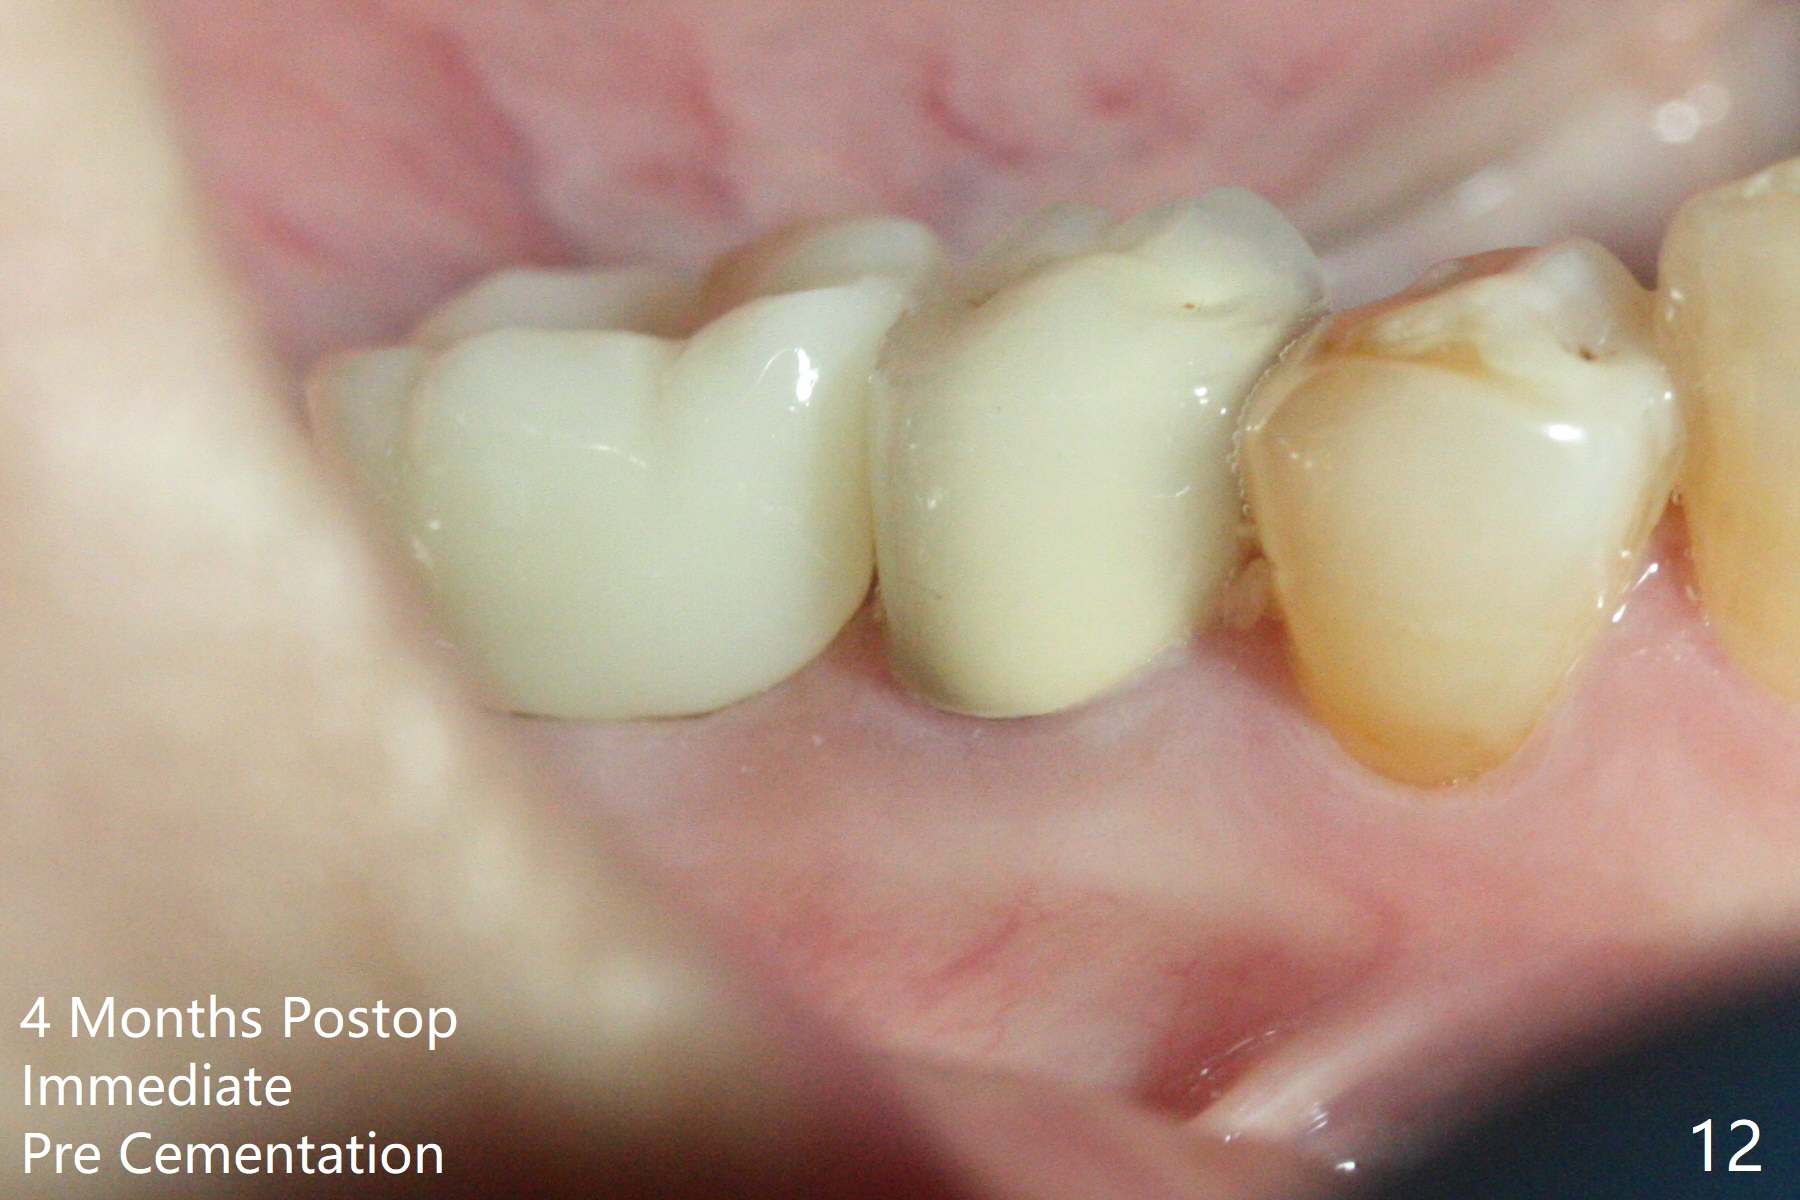

A 59-year-old woman with severe pain and mobility at #30 returns to clinic for extraction and implant on emergency basis (Fig.1 ^: crazing line). To prevent osteotomy deviation off the septum, the crown is sectioned (Fig.2) and the coronal end of the septum is exposed. In fact the initial osteotomy is blind (Fig.3). After increasing the access (Fig.4), trying to change trajectory and increasing the depth and diameter of the osteotomy, the trajectory deviates to the distal socket (Fig.5). Following root extraction, debridement of the sockets and minor trajectory change, a 4x11 mm dummy implant is placed (Fig.6). With a drastic change in osteotomy, the dummy implant position is somewhat acceptable with a 5.2x4 mm planning abutment (Fig.7 P). After placement of bone graft around the 4.5x11 mm final implant to enhance stability, a 5.5x4(3) mm definitive abutment is placed in a restorable position (Fig.8). The implant turns while the abutment screw is hand tightened. Since there is an apical space (Fig.8 <), the implant is then placed ~ 1mm deeper with ~ 30 Ncm (Fig.9). A longer cuffed abutment is inserted and more bone graft is placed (*). In summary, roots in the sockets do not seem to help free hand osteotomy in the lower 1st molar. It is also difficult to control pain during acute infection. Block anesthesia has to be administered, increasing the chance of nerve injury. Either guided surgery or delayed implant should be conducted. There is no postop paresthesia, although the buccal gingiva is slightly erythematou, edematous and tender 1 week posotp. Oral Amoxicillin is prescribed for one more week. The keratinized gingiva (Fig.10 ^) and the papilla (*) are maintained in place around the immediate provisional (P) 2 months 20 days postop. The soft tissue remains normal 4 months postop (Fig.11) and immediate pre cementation (Fig.12).